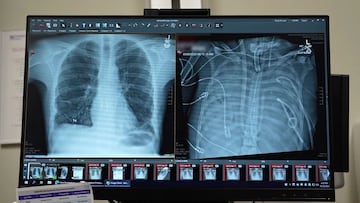

Un hombre de 33 años ha sobrevivido 48 horas sin sus pulmones gracias a un sistema pulmonar artificial externo, desarrollado para mantenerlo con vida hasta que pudiera recibir un doble trasplante de pulmón.

El caso de este hombre surgió porque desarrolló una dificultad respiratoria aguda. Primero le colocaron un respirador, pero no fue suficiente, ya que desarrolló una infección por Pseudomonas aeruginosa resistente a los medicamentos.

Esta infección provocó que sus pulmones se llenaran de pus y entrara en un shock séptico, haciendo que su corazón y riñones comenzaran a fallar.

“Estaba muy enfermo, tuvo un paro cardíaco y se estaba muriendo activamente”, relata Bharat. La situación era tan crítica que no podía recibir un trasplante, por lo que decidieron extirparle los pulmones, la fuente de la infección.

Se mantenía con vida gracias al sistema artificial de respiración, y en 48 horas “había dejado todos los medicamentos para mantener su presión arterial, su función renal se restableció por completo y su corazón estaba funcionando normalmente”, señala Bharat.